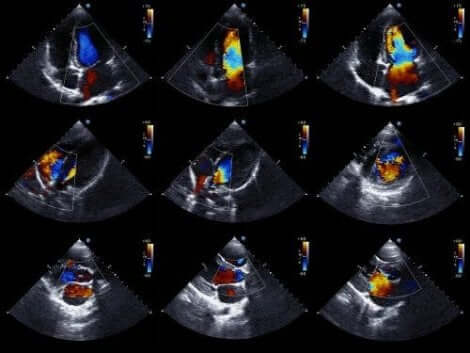

Een echocardiogram is de voorkeurstest om pericardiale effusie te detecteren. Het wordt ook wel een echocardiografie of een cardiale echografie genoemd. Met behulp van deze test kunnen artsen de structuur van het hart zien en het vermogen om bloed rond te pompen bestuderen.

Met het Doppler-echocardiogram kunnen artsen ook de exacte snelheid van de bloedstroom vanuit het hart bepalen. Het tweedimensionale echocardiogram in de M-modus is vanuit technisch oogpunt de ideale techniek voor het diagnosticeren, kwantificeren en bewaken van pericardiale effusie.

Artsen kunnen pericardiale effusie diagnosticeren door de afwezigheid van echo’s tussen het epicardium en het laterale pericardium. Vervolgens bepaalt de cardioloog de grootte van de effusie op basis van de hoeveelheid ruimte tussen de twee lagen van het pericardium.

Deze techniek is een van de meest aangewezen voor hartaandoeningen en de meest gebruikte methode om de opgehoopte vloeistof te kwantificeren. We moeten opmerken dat er in wezen twee soorten echocardiogrammen zijn.

- Er is de transthoracale echocardiogram, waarbij een apparaat op de borst wordt geplaatst, over het hart, en het geeft geluid.

- Daarnaast wordt soms de transesofageale echocardiogram gebruikt, waarbij het apparaat in het spijsverteringskanaal tot aan de slokdarm wordt ingebracht. Dit onderzoek levert meer gedetailleerde gegevens op, maar is ook belastender voor de patiënt.